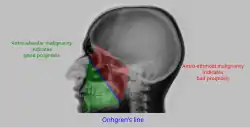

Malignancy

Onhgren's line

• Sinus is radioopaque.

• Sometimes, destruction of walls of sinus is seen and is diagnostic of malignancy

• Distance between antero-lateral wall of maxilla and coronoid process of the mandible is measured. If it is increased on one side, it indicates involvement of infratemporal fossa by the malignancy. This is called Handousa's sign. Prognosis of malignancy is determined by position of tumour on basis Onhgren's line.